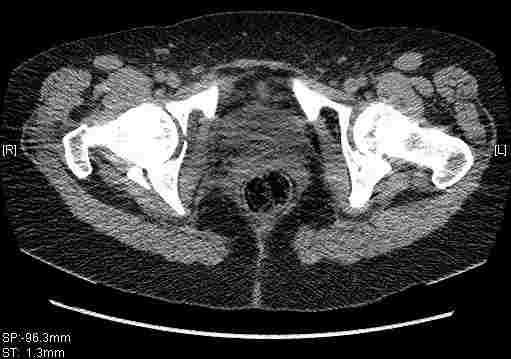

Удалось сегодня вывести пациентку в соседнюю больницу, где есть кт. Срезы сделаны только горизонтальные.

Следом 3d

Приветствую,Антон.Рункова рядом нет,но после полученных данных КТ,обсуждали совместно.Итог обсуждения-развернутый ответ дать не получится,т.к.срезы выбраны не информативные.Если ориентироваться на данные 3D,то ,ИМХО,можно лечить на вытяжении.